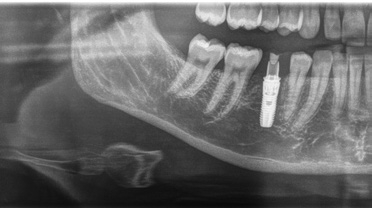

Die intraorale Röntgenaufnahme zeigte die übliche 2-wurzelige Konfiguration des Milchmolaren, apikal das Foramen mentale sowie gering ausgeprägte trabekuläre Strukturen der regionalen Spongiosa aufgrund der kurzen Wurzelkonfiguration (Abb. 2). Eine geführte Implantation, für deren Umsetzung ein DVT angefertigt wurde (Orthophos XG 3D), bot hier den Vorteil einer sicheren Führung ohne Richtungsablenkung durch die bestehenden Alveolen sowie der optimalen Ausnutzung des vorhandenen Raumangebots, um maximale Stabilität zu erreichen. Aufgrund der größeren mesiodistalen Breite des Zahnes 85 im Vergleich zu üblichen Prämolaren orientierte ich mich bei der prothetischen Planung am vorhandenen Milchmolaren.

Nach der geführten Implantatbettaufbereitung wurde das Astra Tech Implant System EV 4,8C × 13 mm durch die Hülse hindurch mit Höhenanschlag in seine geplante Position inseriert (Eindrehmoment final: 45 Ncm) (Abb. 8 bis 10). Die Lage des Implantats wurde mit einer intraoralen Röntgenaufnahme postoperativ überprüft (Abb. 11). Es folgte die digitale Abformung mit der CEREC Omnicam: Um die Implantatposition exakt zu übertragen, wurde ein Scanbody platziert (Abb. 12). Der dabei erzeugte Scan wurde für das präzise Design eines Provisoriums mit der Abformung des Milchzahnes überlagert und im Anschluss gefräst (Abb. 13). Das Kunststoffprovisorium wurde mit der dazugehörigen TiBase verklebt (Multilink Hybrid Abutment, Ivoclar Vivadent). Zuvor wurden sowohl die TiBase als auch das Zirkonabutment sandgestrahlt, im Ultraschallbad gereinigt und im Anschluss silanisiert (Monobond plus, Ivoclar Vivadent). Im nächsten Schritt wurde das Provisorium mit dem Implantat okklusal verschraubt (Abb. 14) und mit Komposit verschlossen (Abb. 15 bis 17). Um eine Überbelastung des Implantats während der Einheilzeit zu vermeiden, war eine Nonokklusion von 0,5 bis 1 mm zum Antagonisten zu beachten. Dazu gehörte auch die Empfehlung an die Patientin, das Provisorium in den ersten Monaten nur eingeschränkt zu belasten (weiche Kost).